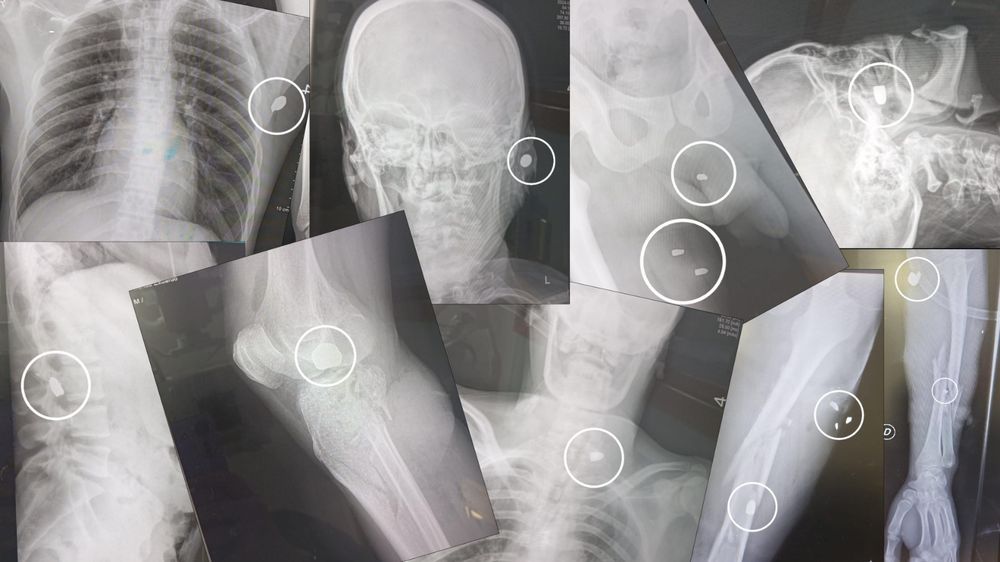

El cadáver estaba perdiendo la rigidez inmediata a la muerte cuando los rayos X detectaron un viejo proyectil muy próximo a la rodilla izquierda. Era una vieja munición, de una balacera anterior, que con el correr del tiempo el propio organismo fue encapsulando como en una coraza de tejido nuevo. Fue una herida de bala de esas que en los diarios se titula: “Internan a hombre lesionado por arma de fuego que no denunció”.

El cirujano Eduardo Nakle lo ve cada día en la mesada del quirófano del Hospital del Cerro. Entran jóvenes —casi siempre son varones de entre 20 y 35 años adictos a la pasta base— con uno, dos y hasta 16 orificios de bala. “Casi la mayoría” habían sido lesionados antes. “Casi la mayoría” fueron baleados en las piernas “porque ese es el código de advertencia” de que la próxima será fatal. “Casi la mayoría” no da detalles de dónde fue herido, a lo que el médico acota en broma que “salían de misa”. Y “casi la mayoría” se recupera al cabo de cuatro días, para luego volver a ese mismo ambiente en que reina el “matar o morir”.

El renovado hospital del Cerro, por solo mencionar uno de los servicios de atención más nuevos, atiende un promedio de un herido de bala por día. “Muchos llegan con varios orificios y muchos con daños importantes de tejidos, porque el fuerza cinética de esas ráfagas de tantos disparos hace destrozos”, explica el cirujano Nakle.

Un disparo de la Glock llega en condiciones óptimas a los 375 metros por segundo. Cuando impacta en un hueso, lo quiebra al instante (con la paradoja de que el hospital del Cerro no cuenta con traumatólogo y tiene que derivar el caso). Y cuando da en una arteria relevante, y la víctima tiene la fortuna de sobrevivir, pierde tanta sangre que requiere “muchas unidades (bolsas) de sangre donada”.